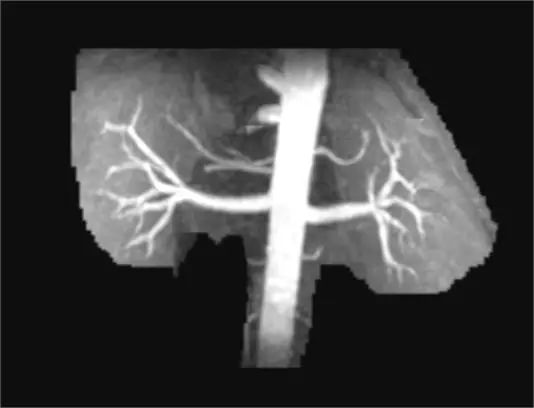

▲正常肾动脉

“这是正常的肾动脉,这是患者徐阿姨的肾动脉。左肾动脉开口处有狭窄。”影像中心袁晨主任表示,非增强型肾动脉磁共振血管显像技术(NE-MRA)是一种安全、无创、准确的检查方式。对高血压、肾动脉狭窄等患者的明确诊断有着重要临床意义。